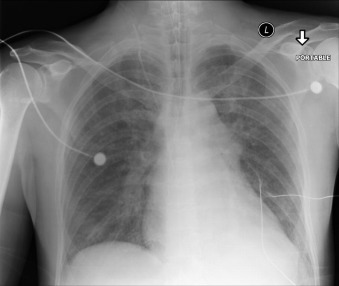

Central Venous Lines ( Figs. 22-1 to 22-13 )

To avoid mechanical irritation (from the catheter tip) and chemical irritation (from infusate) of the right atrium, the catheter tip of a central venous line should be further than the junction of the internal jugular vein and subclavian veins (near the level of the first thoracic rib). In addition, the tip should not be further in than the junction of the superior vena cava and right atrium. Central venous catheters that are intended to record central venous pressure should lie distal to the last venous valves (in the subclavian and internal jugular veins, 2.5 cm proximal to the beginning of the brachiocephalic vein) and before the right atrium. The ideal position of the tip of a peripherally inserted central catheter (PICC) line is in the distal superior vena cava.